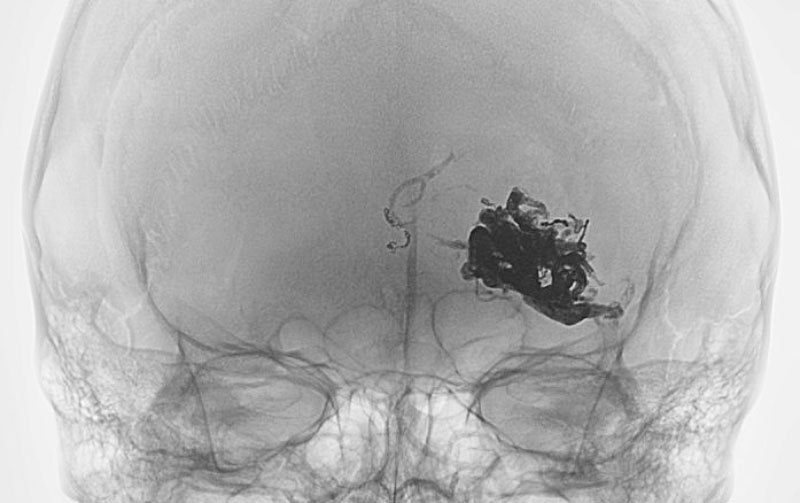

No.1596 手術前

No.1596 手術中

No.1596 手術後

くも膜下出血

左中大脳動脈瘤破裂

40代

救急外来